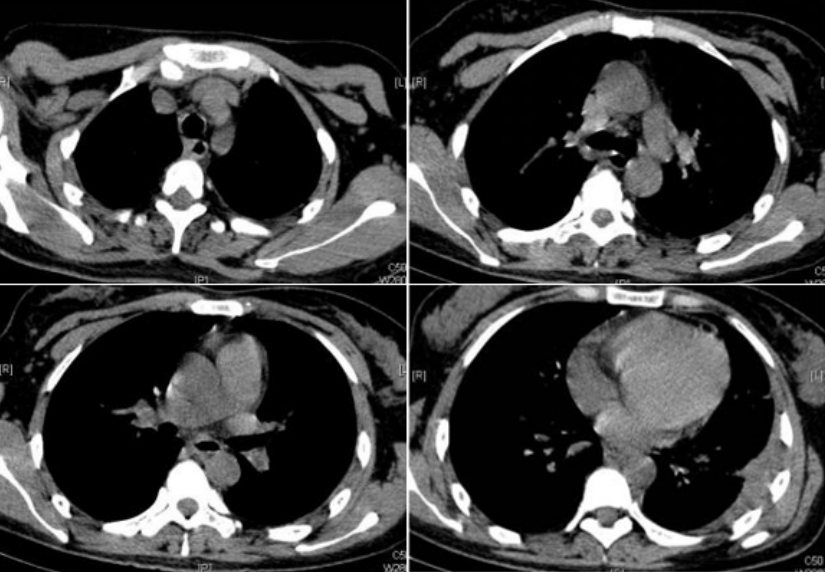

患者入住RICU后监测生命体征,予以碳酸氢钠+奥硝唑注射液胸腔冲洗;予以哌拉西林他唑巴坦+奥硝唑静滴抗感染,同时给予氧疗、补液、护肝等各脏器功能支持治疗。患者严重营养不良,吞咽困难、食欲差,恶心呕吐明显,遂给予肠内联合肠外营养支持。经治疗患者仍高热,4月3日给予经皮纵隔穿刺(图2),抽出约10 ml脓性液体。体温恢复正常3天后再次高热,PPD试验硬结直径小于5 mm,多次胸水抗酸染色未查到抗酸杆菌,多次胸水、血、穿刺液培养均阴性。调整抗感染方案为利奈唑胺+头孢噻利,仍有反复高热,调整抗生素为利奈唑胺+比阿培南,4月12日复查胸部CT考虑可能纵隔脓肿未引流尽,且左下肺积液有包裹(图3),建议患者外科行胸腔镜治疗,患者家属拒绝,故于4月17日行CT引导下经皮胸腔脓肿穿刺抽液,抽出约30 ml暗红色液体,患者体温降至38℃左右,拔除胸腔闭式引流管。患者体温逐渐恢复正常,5月7日再次予左侧包裹脓腔行B超引导下穿刺抽液,抽出约60 ml淡红色液体。5月16日出院后口服抗生素2周。6月14日复查胸部CT吸收理想(图4)。注:A、B、C为右侧颈部、纵隔脓肿及左侧胸腔积液较前吸收,D为左下肺仍有包裹性积液图4 复查胸部CT病灶基本吸收(2012-06-14)